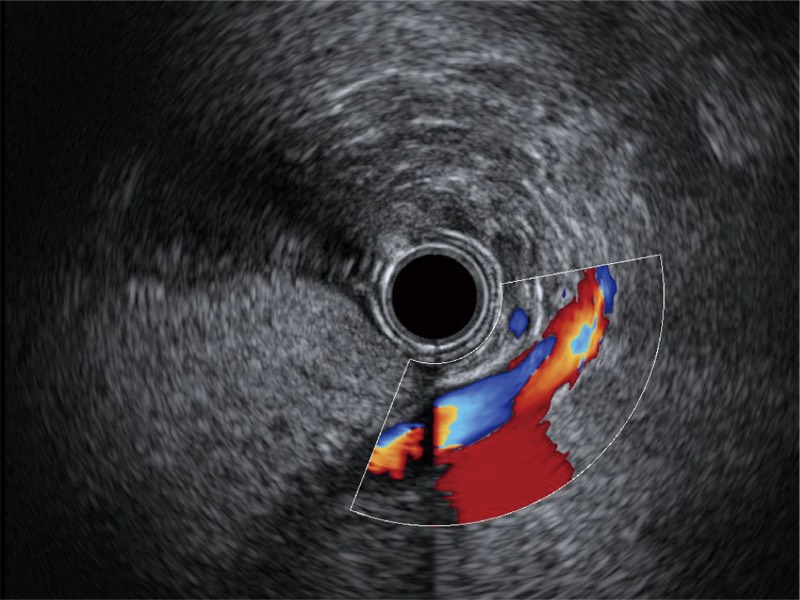

• 清晰显示胆总管及周围血管分布

• 非线性融合造影

融合谐波技术

动态声压控制技术

TIC时间强度分析曲线

具有四种造影成像效果